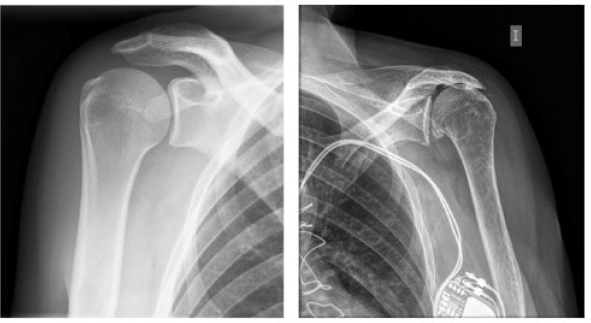

La radiografía simple es fundamental en la evaluación inicial de casi todos los casos de síndrome de hombro doloroso(6). Las proyecciones más informativas incluyen la proyección anteroposterior (AP) verdadera (Figura 2), axial de la escápula u outlet y axilar. Estas proyecciones nos proporcionan detalles clave sobre la estructura ósea y ayudan a determinar la cronicidad de la condición.

Figura 2: Radiografía de Hombro anteroposterior verdadera. (A) Radiografía normal. (B) Moderada artrosis glenohumeral y marcada disminución de amplitud del intervalo acromio-humeral.